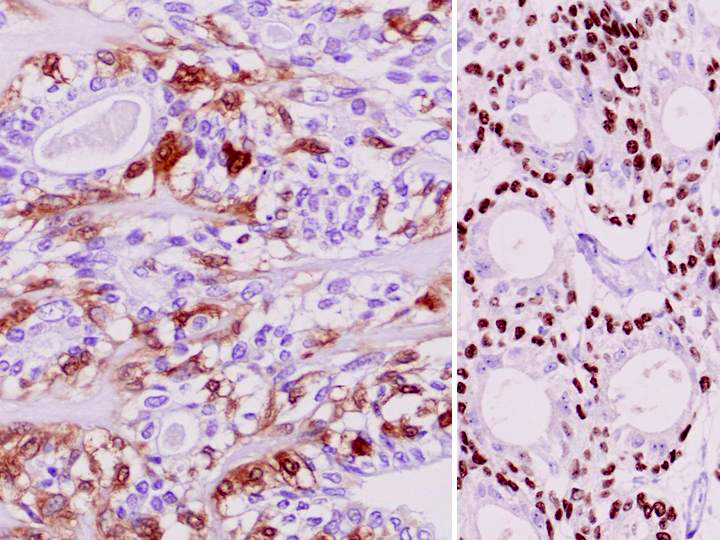

| 外層の筋上皮は免疫組織化学的にS100蛋白(左)およびp63(右)に陽性を呈する. |